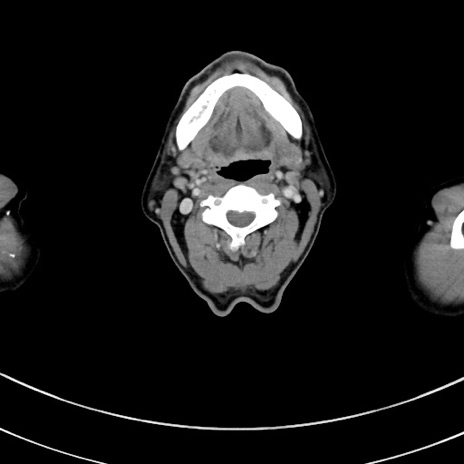

症例8(横断像)

【症例】 60歳代男性

【主訴】 黒色吐物

【現病歴】 4日前から嘔気自覚、2日前の朝食後にも嘔気あり、自分で手で嘔吐反射起こし嘔吐したところ血が混ざっていたため受診。

【既往歴】 5年前汎発性腹膜炎を伴う急性虫垂炎で手術、高血圧、前立腺肥大症、高脂血症

【身体所見】 腹部正中に手術癩痕あり 腹部平坦・軟圧痛なし膨満感あり

【データ】WBC 8400、CRP 4.54